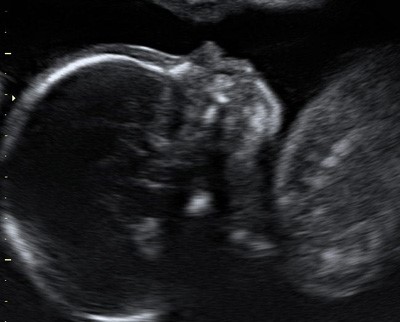

На фото УЗИ беременной видна только голова и верхняя часть туловища плода, четко виден профиль, носовая кость и ТВП. Достаточно часто можно увидеть такие некорректные изображения:

На этих изображениях плод лежит криво, увеличение изображения недостаточное, нельзя увидеть четкий профиль плода. Измерение ТВП в таких изображениях НЕКОРРЕКТНО и приводит к завышению или занижению риска болезни Дауна!!!